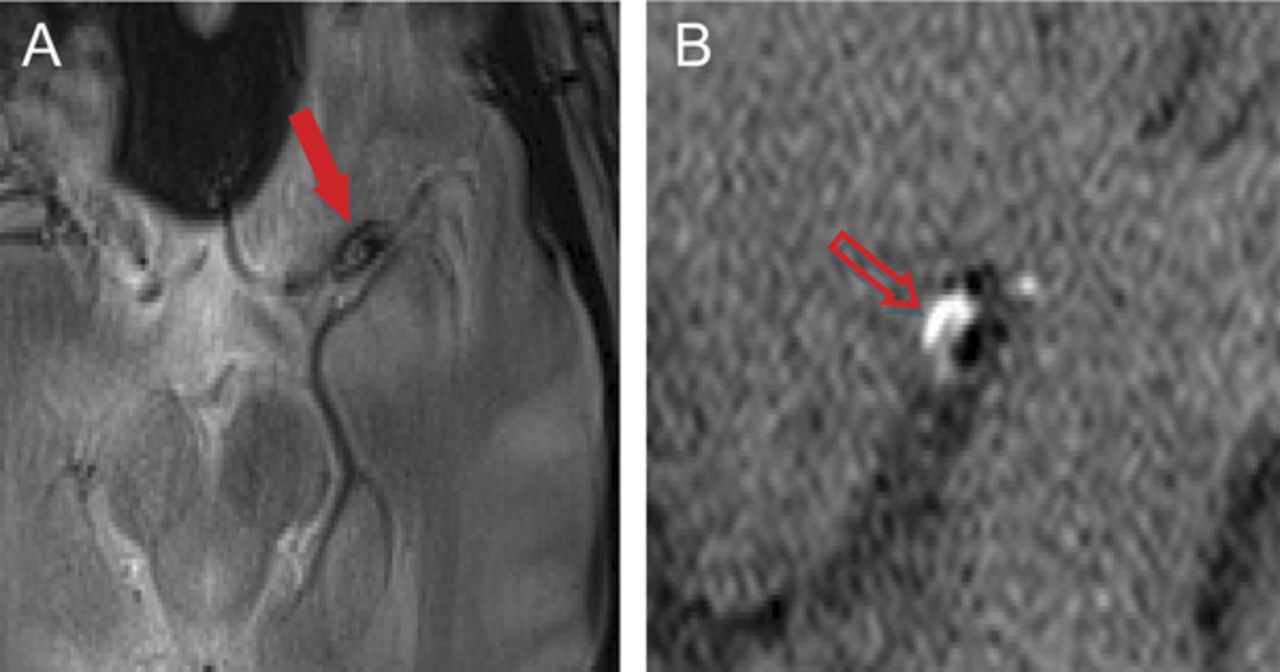

一个29岁的男人面对单边轻微的头痛3天,类似于以前的头痛,但与进行性加重;没有前期感染或创伤。MRI显示左striatocapsular梗死(图1一个),没有证据表明cardioembolism或血管炎。数字减影血管造影显示左大脑中动脉(MCA)狭窄的树干(图1 b)。校内的血肿显示动脉解剖。1膨胀的校内的血肿在T2 *与一个古怪的高信号边缘上矢状t1加权成像,沿着前上的MCA动脉穿支的起源(墙图2)。诊断是自发MCA解剖。

图2

影子从校内血肿迹象

低信号强度(箭头),在左边M1树干在T2 *图像(“影子标志”)和高信号边缘(B,空心箭头)的中期部分左大脑中动脉在矢状高分辨率t1加权图像。